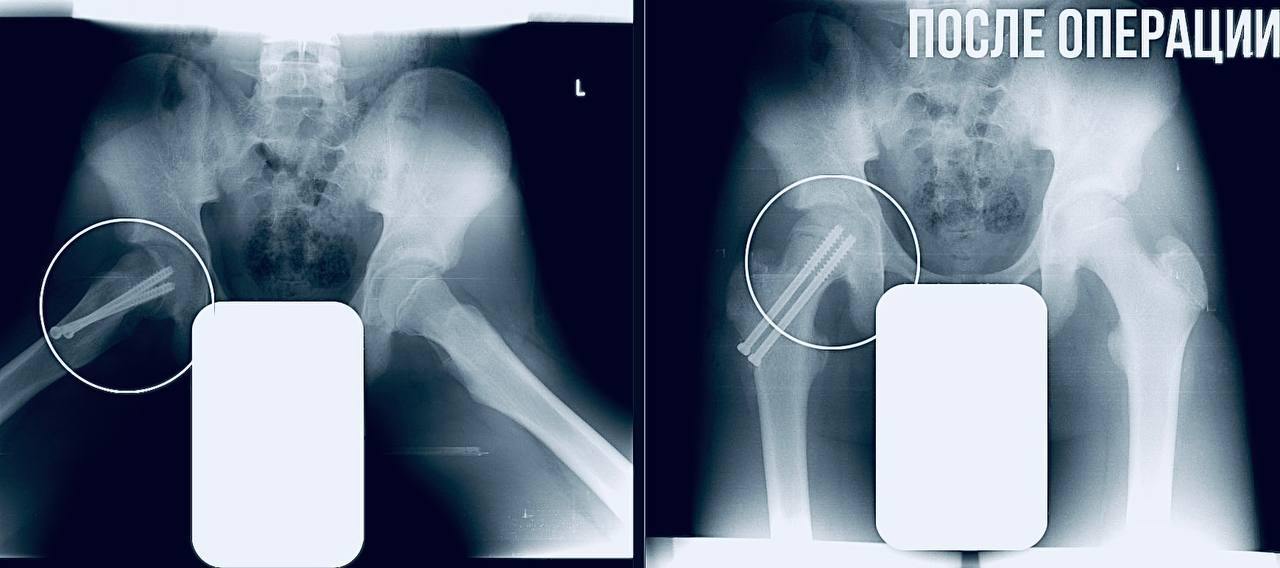

В ходе обследования выяснилось, что у подростка – юношеский эпифизеолиз.

Патология подразумевает смещение головки бедренной кости, характерное для периода активного роста скелета.

— Пациенту требовалась срочная операция. Мы выполнили фиксацию сустава, чтобы остановить смещение и дать ему возможность правильно развиваться. Это убережет юношу от раннего артроза и ограничений подвижности в будущем, — отметил главный врач МОДКТОБ Александр Григорьев.